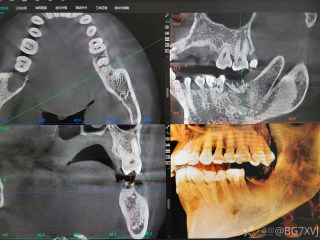

2023年10月26日,来自山东菏泽市成武县的小烨和他家人的命运被彻底改变了。这个原本阳光、可爱的小男孩在一次意外被撞击后,在医院检查出了腹腔内存在肿瘤,并在手术中被切除了包括十二指肠、胰腺、大部分胃和小肠等多个器官。此后便无法再像正常人一样吃饭、喝水,活着要靠长期静脉注射营养液。一份2024年12月由第三方机构出具的司法鉴定意见书显示,当时给小烨做手术的成武县人民医院在该医疗行为中存在过错,与小烨的损害后果之间存在因果关系,建议医疗过错在损害后果中的原因力大小为同等原因。此外,另一份由成武县卫生健康局在2025年9月28日发出的书面答复中显示,成武县人民医院存在24小时内未完成病历;手术知情